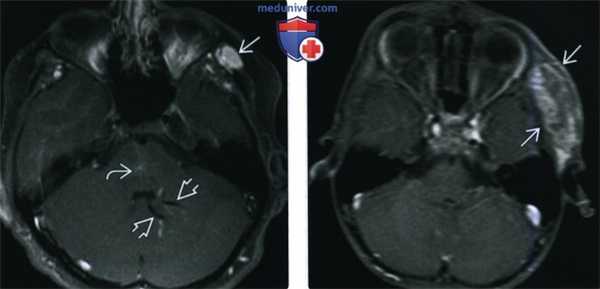

Гемангиома правой глазницы с кровоизлиянием в опухоль (стрелка: уровень жидкости). На Т1 - (а) и Т2-взвешенном изображении (b) визуализируется объемное образование, расположенное внутри конуса, образованного глазодвигательными мышцами. На П-взвешенном изображении (с) после введения гадолиния наблюдается незначительное усиление сигнала от опухоли.

3. МРТ при лимфатической мальформации глазницы:

• Т1 ВИ:

о Дольчатое образование с нечеткими контурами

о Содержимое многокамерных кист - различной давности геморрагическое, лимфатическое или белковое - формирует уровни жидкость - жидкость и дает вариабельный сигнал

о Продукты распада крови различной давности, а также кровь, излившаяся в результате подострого кровоизлияния, дают гиперинтенсивный сигнал

• Т2 ВИ с подавлением сигнала от жира:

о Дольчатое образование, гиперинтенсивный сигнал от жидкости

о Параметры сигнала от уровней «жидкость-жидкость» зависят от сроков существования продуктов распада крови

о Потери сигнала нет (в отличие от инфантильной гемангиомы)

• Т1 ВИ с контрастированием и подавлением сигнала от жира:

о Контрастирование вариабельно, как правило, по краю кист наблюдается контрастный ободок

о При наличии развитого венозного компонента отмечается более интенсивное неравномерное контрастирование

о При остром увеличении может выявляться неконтрастируемый тромб